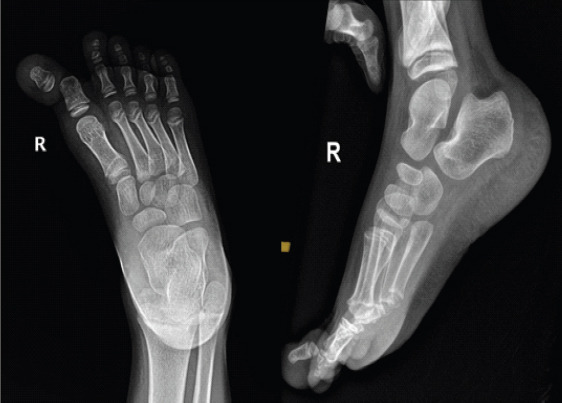

Case report: We report a case of open HIP joint dislocation in a 7-year-old boy surgically managed with irrigation and debridement and K-wire fixation. The HIP joint was found to be stable at 4 weeks after K-wire removal and the patient had full, painless HIP joint range of motion at 24 weeks.